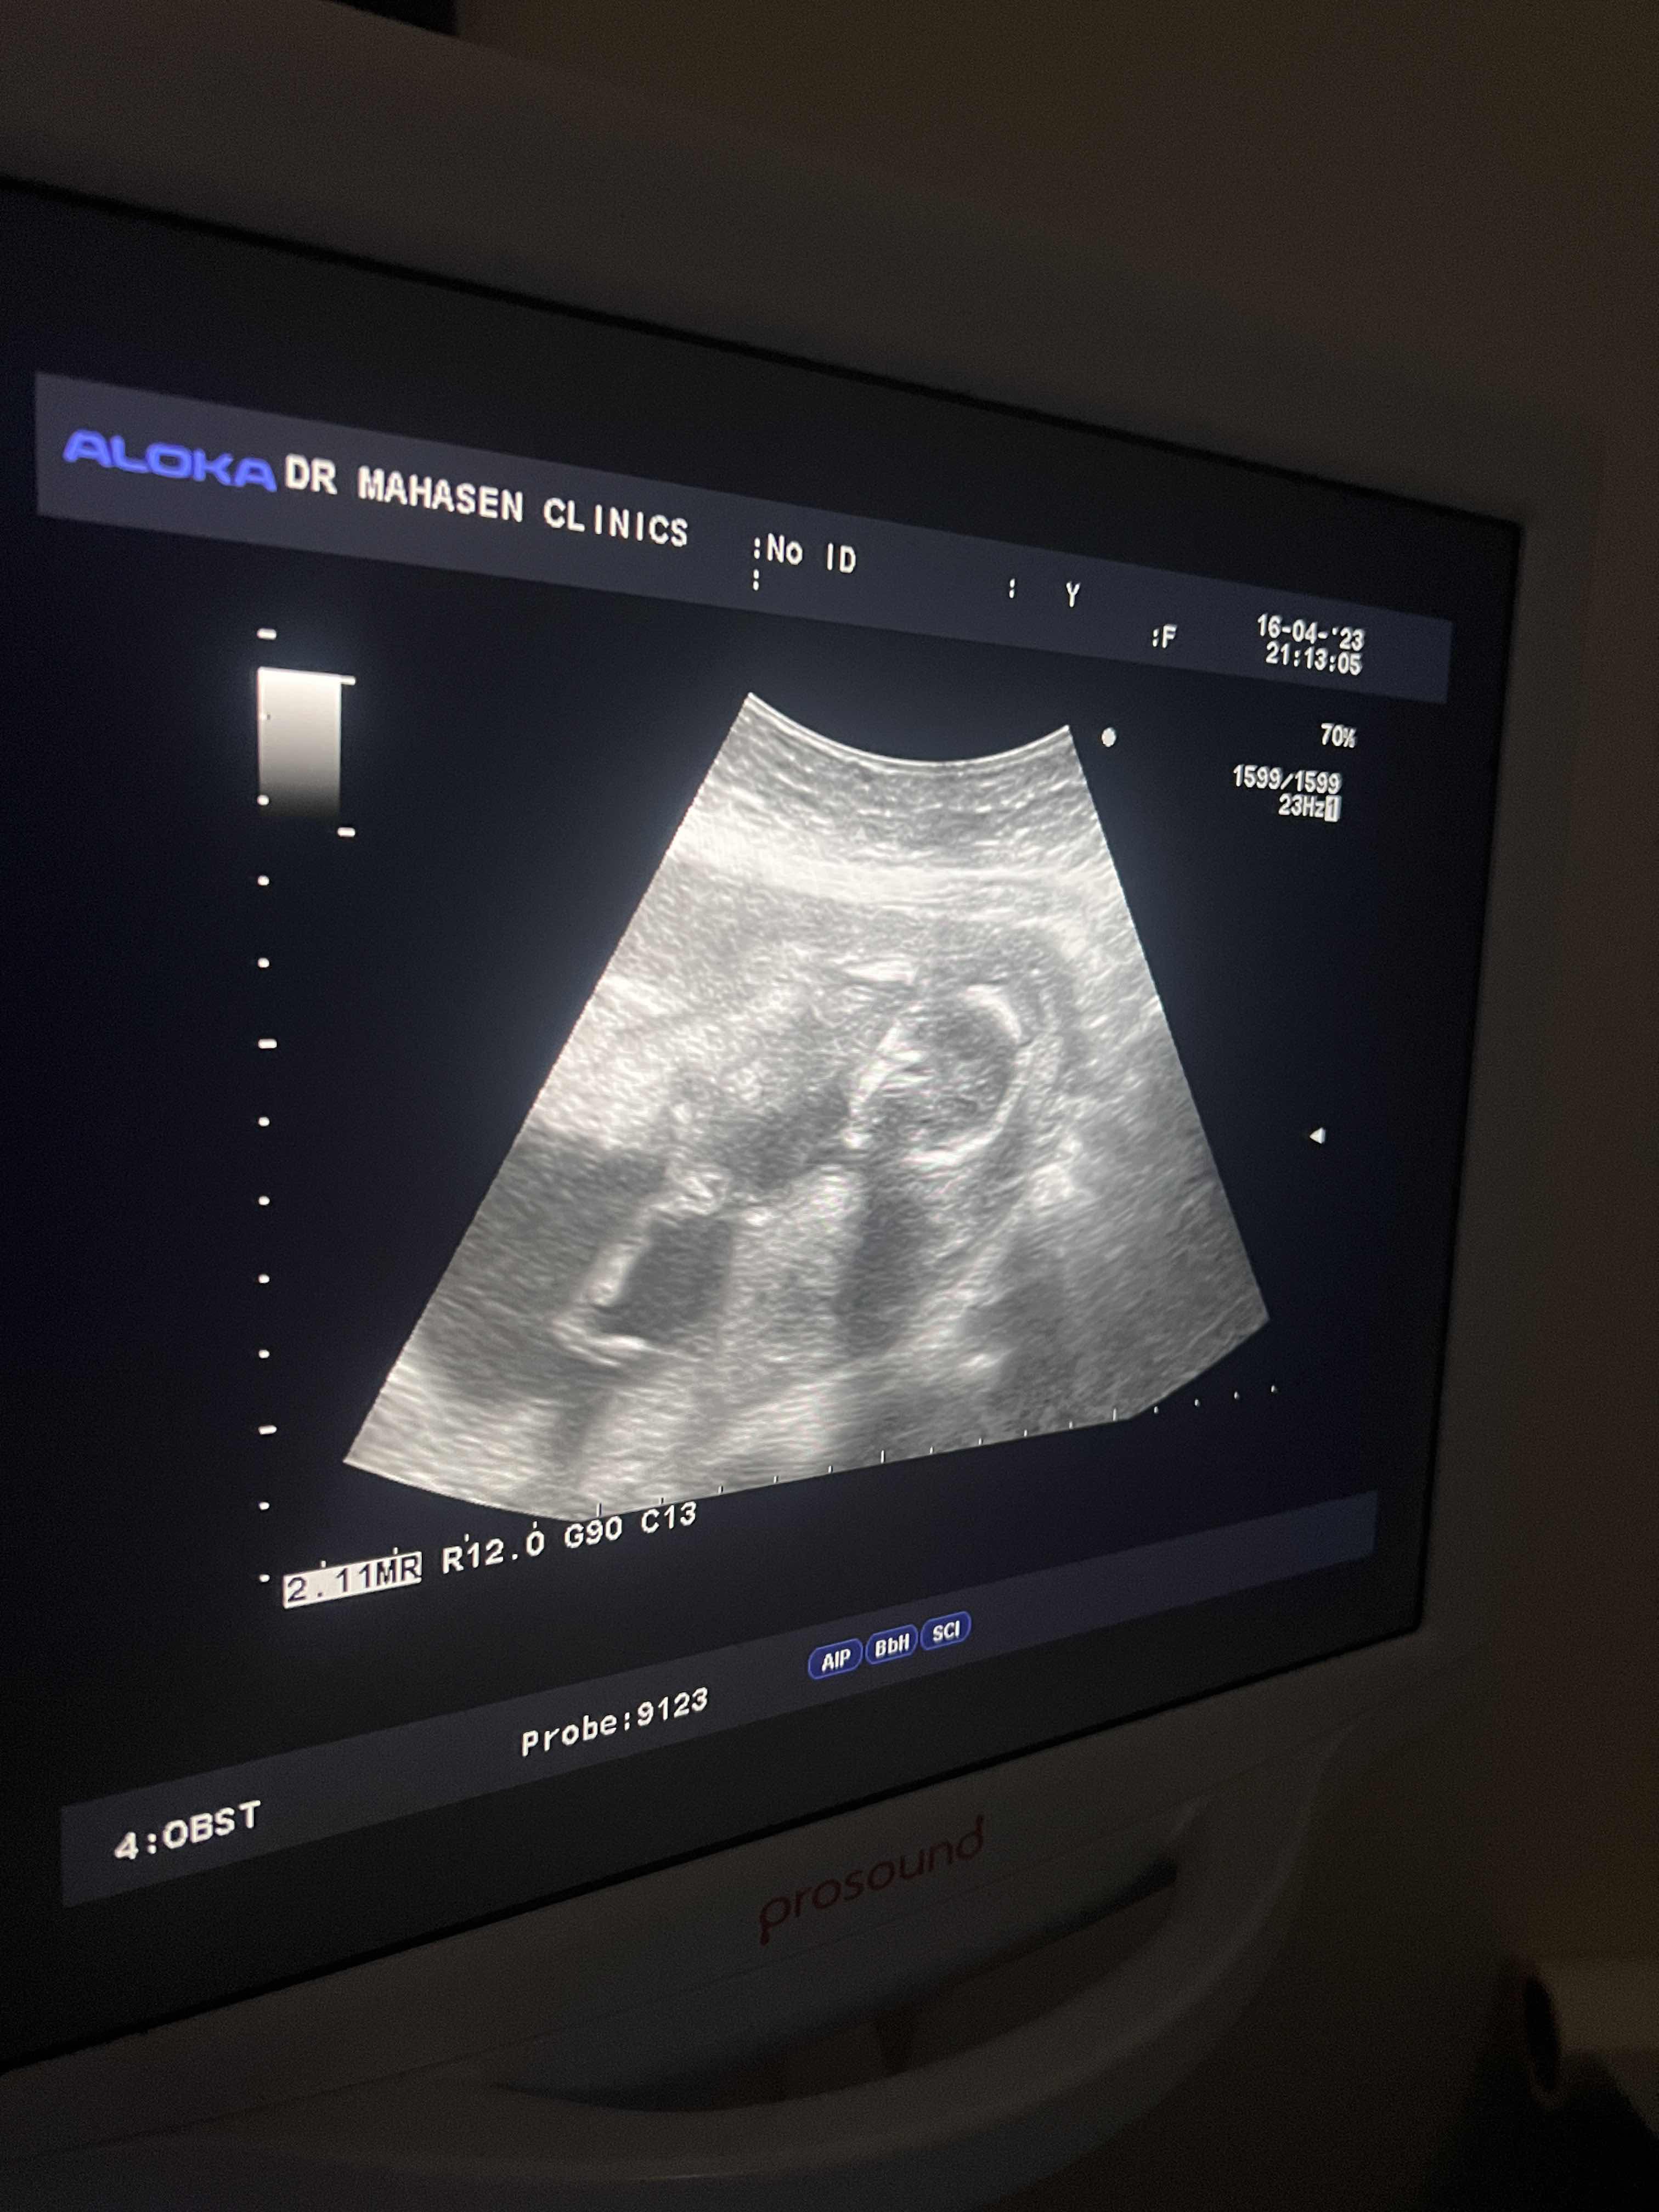

ماجنس الجنين ذكر ام انثى